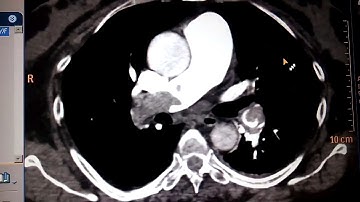

CT pulmonary Angiography Procedure. Detailed Explanation part-2 @avnishradiology